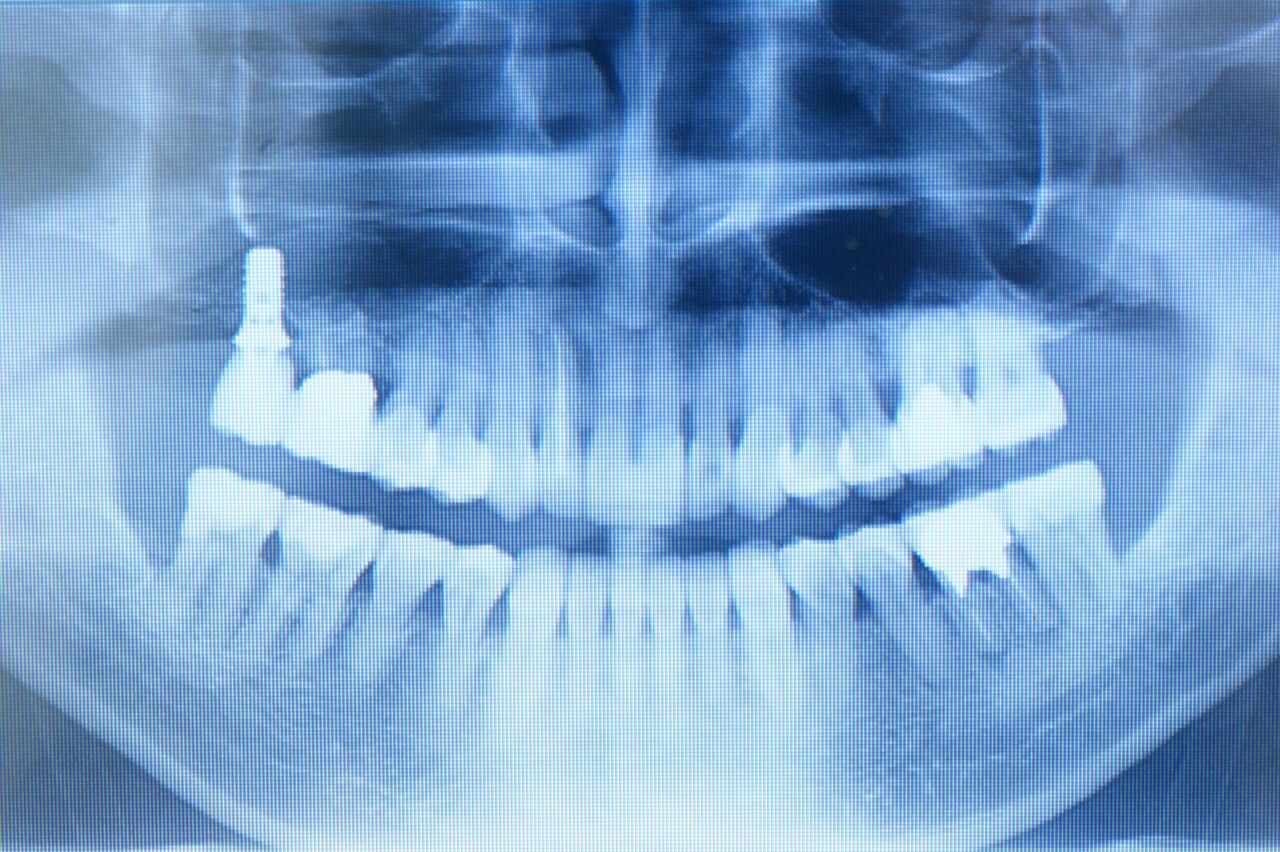

前回のブログの概略を説明しますと、患者さんは初診時53才、男性、会社役員、右上臼歯部の違和感を主訴として来院。通法に従い精密検査終了後問題点を抽出したところ、全体的に歯周病が中~高程度に進行しており、特に咬合において鋏状咬合(Scissors bite)であることが原因となり主訴につながっていると診断。

初期治療後、再評価すると歯周ポケットが(一歯につき六点法で)初診時4mm以上131ポイントが53ポイントに(保存不可能歯の抜歯あり)減少。患者さんに再度報告説明して理解を得、必要な歯周外科を四回にわたり施行。再評価すると歯周ポケットが13ポイントに減少。この時点での4mm以上の意味する処は診査時出血等の炎症因子もなく、歯周組織が治癒しつつある状態と判断し矯正治療に移行。

矯正治療終了後、模型を咬合器に付着し診断用ワクシングをしたところ、本来歯牙は咬合調整か小規模の修復処置で済めば極力そのまま使うのが理想ではあるが、長年の不正咬合とブラキシズムによる高度の磨耗のため、修復処置なしでは安定した咬合に基づく長期的な口腔内の健康は得られないとの判断に至る。

一口腔単位の長期的な健康維持のため、安定した咬合の確立と審美性の獲得を意図し全顎的修復処置を行う。(大)